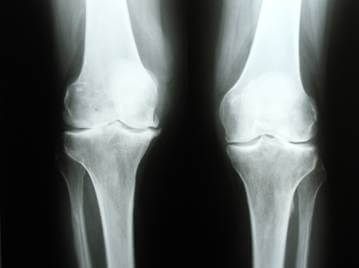

Правильность постановки диагноза будет зависеть от четкости снимков и отображения на них необходимых частей коленного сустава в разных проекциях. Однако такие критерии зависят не только от основных особенностей рентгенологического оборудования. Чаще информативность снимков больше зависит от компетентности доктора-рентгенолога. Именно врач может определить, в каких проекциях нужно сделать снимок коленного сустава.

Обычно одного снимка для постановки диагноза недостаточно, а требуется проведение рентгена как минимум в двух проекциях.

1. В прямых проекциях можно обнаружить переломы. Для этого пациента укладывают на специальный стол.

2. Снимки в тангенциальных проекциях делают в положении пациента стоя. Они показывают изменения, связанные с патологическими процессами и поражением суставной поверхности, надколенника.

3. В боковых проекциях, когда снимок делают в положении стоя, видны изменения с надколенниковой сумкой и выпот с этой стороны.

4. При чрезмыщелковых проекциях диагностируется гонартроз, разрыв связок или некроз тканей.

Конечно, если снимки делают в двух проекциях, цена на диагностику увеличивается.